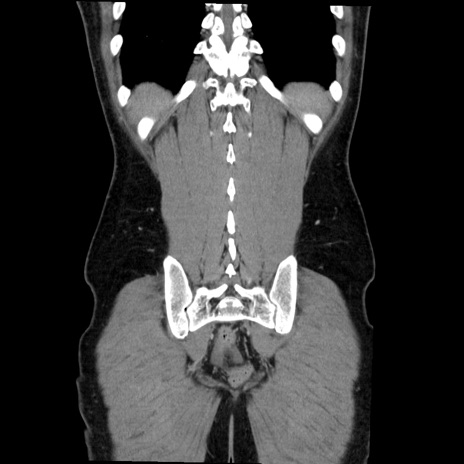

症例36(冠状断像)

【症例】20歳代 男性

【主訴】心窩部痛

【現病歴】今朝より上腹部痛あり。一旦軽快していたが再度出現したため救急要請。昨日夕に白身の魚を含む刺身を食べた。

【身体所見】BP 136/89mmHg、HR 74/min、BT 37.0℃、腹部:膨満、軟、心窩部に圧痛あり。反跳痛なし、筋性防御なし、腸雑音やや亢進あり。

【データ】WBC 17700、CRP 0.48